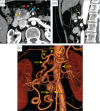

A 71-year-old woman presented to our hospital because pancreatic head cancer was suspected on a medical checkup. Computed tomography showed a 30 mm low-density lesion in the pancreatic head, and the stenosis of the celiac axis (CA) due to the median arcuate ligament (MAL) compression. We made a preoperative diagnosis of pancreatic head cancer and performed laparotomy. Transection of the MAL failed to restore adequate hepatic arterial flow, necessitating arterial revascularization, which was achieved by end-to-end anastomosis between the gastroduodenal artery and the middle colic artery. After reconstruction, Doppler ultrasonography showed improved hepatic arterial signal. The patient was discharged 16 days after surgery with no complications. When planning pancreaticoduodenectomy (PD) for such patients with CA stenosis due to MAL compression, surgeons should simulate a situation of insufficient hepatic arterial flow after division of the MAL, and prepare for reconstruction of the hepatic artery during PD.